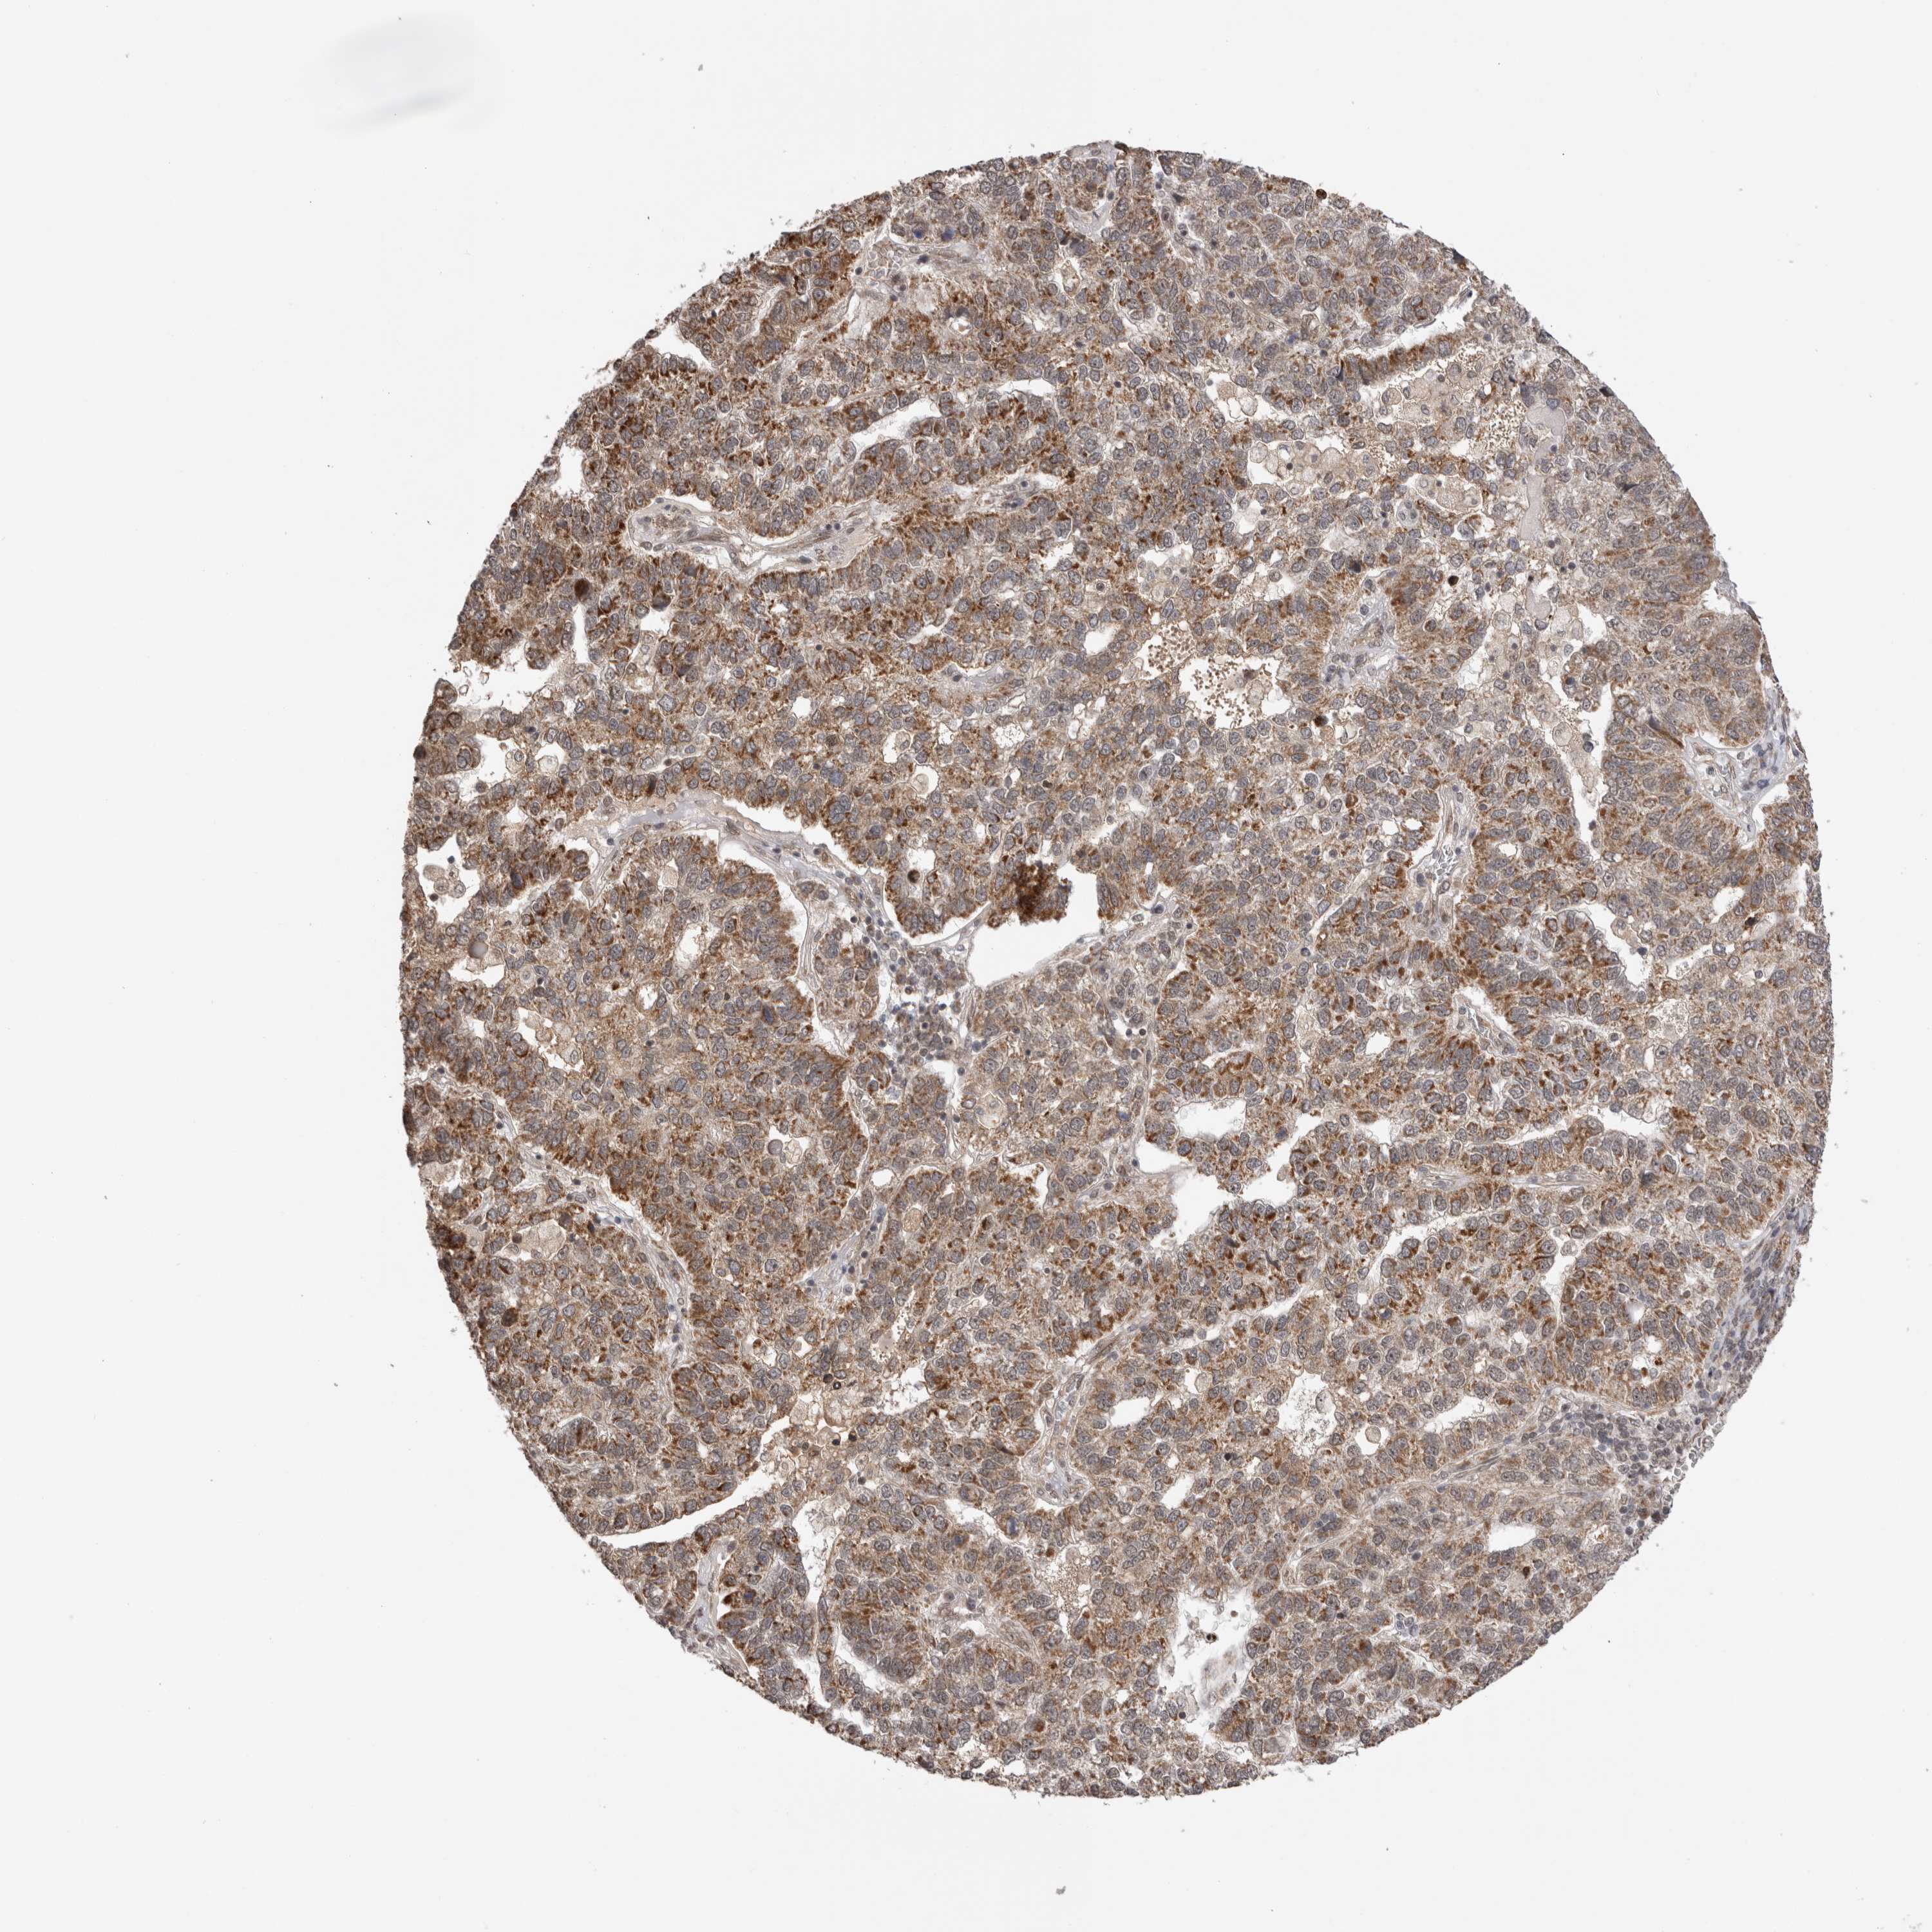

PANCREATIC CANCER - Protein expressioni

A mouse-over function shows sample information and annotation data. Click on an image to view it in a full screen mode. Samples can be filtered based on level of antibody staining by selecting one or several of the following categories: high, medium, low and not detected. The assay and annotation is described here.

Note that samples used for immunohistochemistry by the Human Protein Atlas do not correspond to samples in the TCGA dataset.

Antibody stainingi

Antibody staining in the annotated cell types in the current human tissue is reported as not detected, low, medium, or high, based on conventional immunohistochemistry profiling in selected tissues. This score is based on the combination of the staining intensity and fraction of stained cells.

Each image is clickable and will lead to virtual microscopy that enables deeper exploration of all samples and also displays staining intensity scores, fraction scores and subcellular localization as well as patient and tissue information for each sample.

Antibody HPA025020

Staining

High

Medium

Low

Not detected

Intensity

Strong

Moderate

Weak

Negative

Quantity

>75%

75%-25%

<25%

None

Location

Nuclear

Cytoplasmic/membranous

Cytoplasmic/membranous,nuclear

Adenocarcinoma, NOS